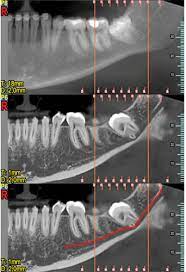

Der eine Nerv ist der Nervus alveolaris inferior der unterste Ast des Trigeminus-Nervs. Hatte ich noch nie eine Spritze im Mund. Weisheitszahn und zyste nerv nah - risiko.

Häufig verläuft ein Nerv entweder durch die Wurzeln oder am Zahn entlang. Und bei nicht wenigen war es der fall dass der eingriff nah am nerv vorgenommen wurde das risiko also da war. Bevor ich meinen körper über jahre mit schmerzmitteln schädige und schmerzen leide würde ich mich diesem eingriff unterziehen.

Sie liegen sehr nah am Nerv weshalb der Arzt nur zwei auf Einmal zieht. Bei der lokalen Narkose besteht das Risiko vor allem dadurch dass durch die Nadel ein Nerv beschädigt wird.